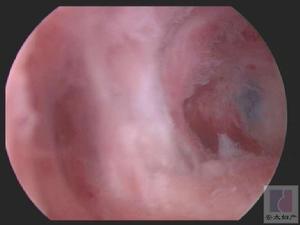

(五)腹腔镜检查 可直接观察子宫输卵管和卵巢的形态,并可作卵巢活组织检查,对诊断卵巢早衰或多囊卵巢综合征有帮助。 医学百科网 | YxBaike.Com